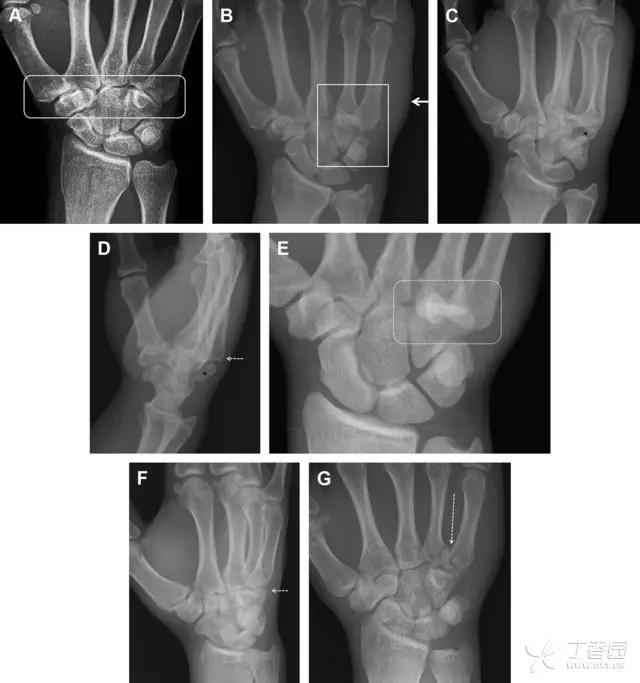

31 舟状骨骨折

舟状骨骨折 60%~70% 发生于腰部,15% 发生于近极, 10% 发生于远极, 8% 发生于远端关节面。除了常规的前后位、侧位、斜位片外,还需要拍专门的舟状骨位片(腕关节尺偏,以舟状骨为中心的腕关节前后位片),特别是鼻烟壶有压痛时。

图 2 舟状骨骨折 (A、B)第 1 例患者,舟状骨远极关节内骨折(白色箭头),斜位片显示较清楚(B);(C、D)第 2 例患者,舟状骨腰部骨折(虚线箭头),斜位片显示较清楚(D);(E~H)第 3 例患者,舟状骨近极骨折,常规 X 线片均未看到骨折,而在舟状骨位片上才能见到骨折(虚线圆)